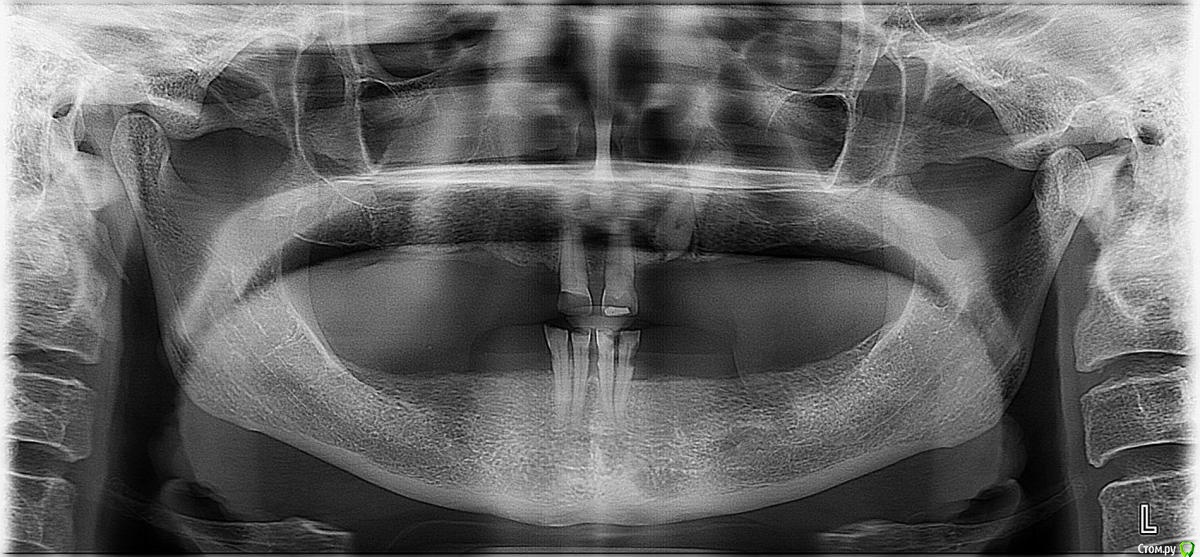

Chernykh Опубликовано 26 мая, 2018 Поделиться Опубликовано 26 мая, 2018 Друзья, моя родственница 56 лет, которая живёт в деревне Ставропольского края крайне нуждается в улучшении качества жизни в плане зубов.Их у неё осталось 6, а хочется иметь все!Подскажите, пожалуйста, как ей исправить эту грустную ситуацию с зубами?Было бы здорово дать возможность бабушке на пенсии вернуть шансы похрустеть яблоками и огурцами.Снимок ОПТГ прилагаю.Очень ждём ваших советов и комментариев. Ссылка на комментарий

Chernykh Опубликовано 27 мая, 2018 Автор Поделиться Опубликовано 27 мая, 2018 Если бабушка варианты с имплантацией не рассматривает,то в данном случае это будут только два полных съемных пластиночных протеза.По поводу похрустеть яблоками не обещаю,хотя при очень хорошем исполнении все возможноСпасибо за комментарий!А нужно ли что-то делать с оставшимися зубами?Может быть их нужно пролечить? По её ОПТГ нет никаких комментариев?А может быть вообще разумно и их удалить что бы сделать протезы полных челюстей? Ссылка на комментарий

chervoncevdaniil Опубликовано 27 мая, 2018 Поделиться Опубликовано 27 мая, 2018 Спасибо за комментарий!А нужно ли что-то делать с оставшимися зубами?Может быть их нужно пролечить? По её ОПТГ нет никаких комментариев?А может быть вообще разумно и их удалить что бы сделать протезы полных челюстей?Разумнее удалить,потому что исходя из уровня костной ткани они скорее всего подвижны и как опора долго не отслужат и придётся все равно удалять и повторно начинать протезирование и привыкание сначала Ссылка на комментарий

brg Опубликовано 27 мая, 2018 Поделиться Опубликовано 27 мая, 2018 (изменено) Их у неё осталось 6Обрадуйте родственницу у нее СЕМЬ зубов. Изменено 27 мая, 2018 пользователем brg 3 Ссылка на комментарий

DoctorT Опубликовано 29 мая, 2018 Поделиться Опубликовано 29 мая, 2018 (изменено) Все там помещается (для уточнения сделал бы компьютерную томограмму), погуглите методику имплантации all on four. В 56 явно еще не бабушка! Вкратце: на каждую челюсть по 4 имплантанта под определенными углами, к ним сразу протез прикрутить винтами, получаем все зубы (обычно по 12 вверху и внизу). Все это займет 2 дня. С оставшими зубами придется расстаться. Изменено 29 мая, 2018 пользователем DoctorT Ссылка на комментарий

DmitrySH Опубликовано 30 мая, 2018 Поделиться Опубликовано 30 мая, 2018 А нужно ли что-то делать с оставшимися зубами? Может быть их нужно пролечить? По её ОПТГ нет никаких комментариев? А может быть вообще разумно и их удалить что бы сделать протезы полных челюстей? Такое кол-во зубов уже вносит элемент ненадежности в протезирование. И усложняет его. Ссылка на комментарий